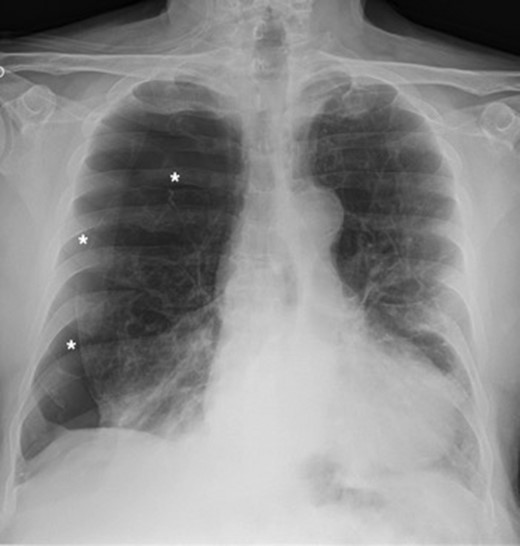

A 73-year-old male patient with a clinical history of COPD, lung emphysema and a 30-year smoking history was admitted to the ED due to a 24-h clinical picture of dyspnea immediately following a sudden bout of dry coughing. Physical examination showed a dyspneic patient, tachypnea of 25 rpm, heart rate of 85 bpm and blood Pressure of 135/75 mmHg along with central cyanosis. Chest exam showed a hyper-resonant right hemithorax along with reduced breath sounds. Initial chest X-ray revealed a large right-sided pneumothorax (Fig. 1). A right chest tube was placed in the ED. Emergency echocardiogram had no significant findings and spirometry showed suspected patterns of obstruction. Following patient stabilization, a high-resolution chest computed tomography (HRCT) was performed revealing extensive pan lobar emphysema throughout both lungs, para septal emphysema in both the anterior upper lobes and herniation of a left lung bullae through the anterior mediastinal pleura along with a right-sided pneumothorax with the chest tube in place with persistent air space (Fig. 2). The patient was taken to surgery where a right video-assisted thoracoscopic (VATS) approach showed severe lung emphysema and a contralateral herniated left lung bulla through the mediastinal pleura anterior to the pericardium (Fig. 3). Right pleurodesis was performed using Talc and a left posterior thoracoscopy showed a severe emphysematous left lung with a lingular herniated bulla to the right hemithorax through an anterior mediastinal pleural defect along with pleural adhesions (Figs 4 and 5). Thoracoscopic hernia reduction was performed along with bullectomy using 60 mm mechanical sutures (Fig. 6). Chest tubes were removed on POD 3 (right) and POD 4 (left). The patient had significant respiratory improvement and was discharged on POD 5.